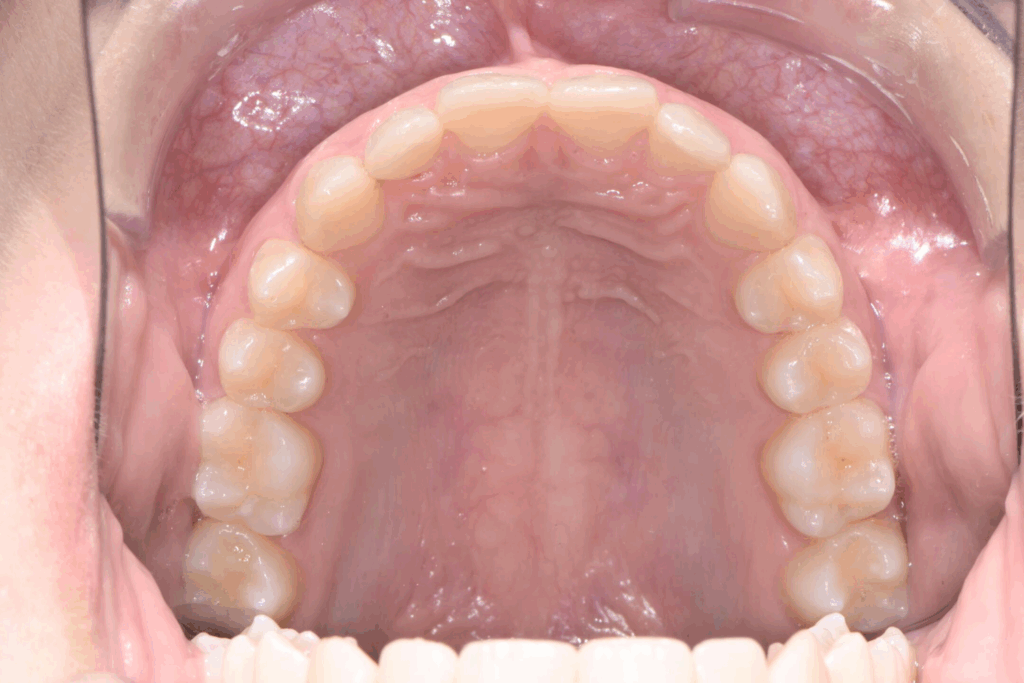

La prima fase del trattamento è stata un’analisi approfondita. Durante il check-up, abbiamo confermato la diagnosi di agenesia dei secondi molari permanenti inferiori, una condizione congenita che lascia spazi vuoti nell’arcata. Abbiamo inoltre rilevato che gli incisivi superiori erano di dimensioni ridotte rispetto al resto dei denti e che la paziente presentava un morso profondo, con gli incisivi superiori che coprivano eccessivamente quelli inferiori. Questa valutazione completa ci ha permesso di creare un piano di trattamento personalizzato e preciso, tenendo conto di tutte le problematiche presenti.

Fase 2: prima della ricostruzione in composito

Una volta completata la fase ortodontica, siamo passati alla finalizzazione estetica degli incisivi superiori. Utilizzando la tecnica della ricostruzione in composito, abbiamo aumentato le dimensioni dei denti, migliorandone la forma e l’armonia con il resto del sorriso. Il composito, un materiale estetico e versatile, ci ha permesso di ottenere un risultato naturale e duraturo senza sacrificare la struttura dentale originale.

Risultato finale